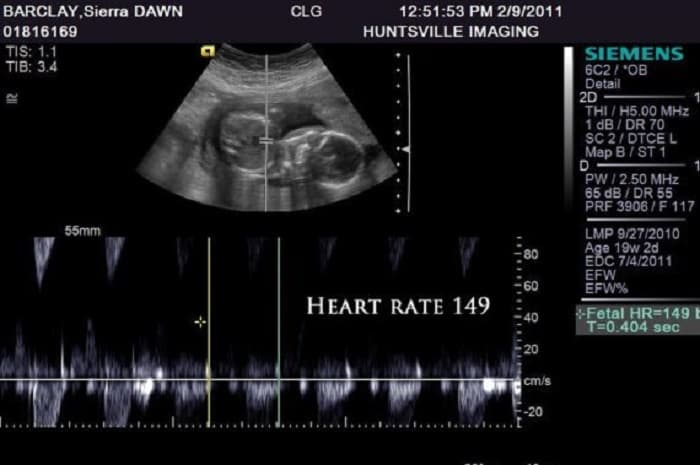

Ở tuần thứ 7, tim thai bắt đầu phân chia thành buồng trái và phải. Bác sĩ có thể nhìn thấy và đo được những điểm sáng nhấp nháy trên máy siêu âm. Ở giai đoạn này, nhịp tim của bé rơi vào khoảng 90-110 nhịp/ phút. Nhịp tim của bé đạt đỉnh cao nhất vào khoảng tuần 9, từ 140-170 nhịp/phút. Các tuần thai sau này, tim của bé sẽ hoàn chỉnh hơn về cấu tạo và chức năng cũng như kích thước. Giai đoạn này, nhịp tim của bé sẽ vào khoảng 120-160 nhịp/ phút.

Ở tuần thai này, nhịp tim của bé có thể gấp đôi nhịp tim của mẹ và vào khoảng 150-170 lần/ phút.

Giai đoạn tuần 7, 8, 9, 10: trong suốt khoảng thời gian này, nhịp tim của bé sẽ tăng lên đáng kể. Đây là dấu hiệu cho thấy mọi thứ hoàn toàn bình thường. Ở tuần thứ 6, nhịp tim là 110 nhịp/phút, sau đó nó sẽ tăng trong tuần thứ 7 và đạt mức 170 nhịp/phút ở tuần 9-10. Nhịp tim này tiếp tục duy trì trong 4 tuần tới.

Giai đoạn tuần 11, 12, 13, 14: Đến tuần thứ 14, nhịp tim bắt đầu giảm từ 170 nhịp/phút xuống còn 150 nhịp/phút.